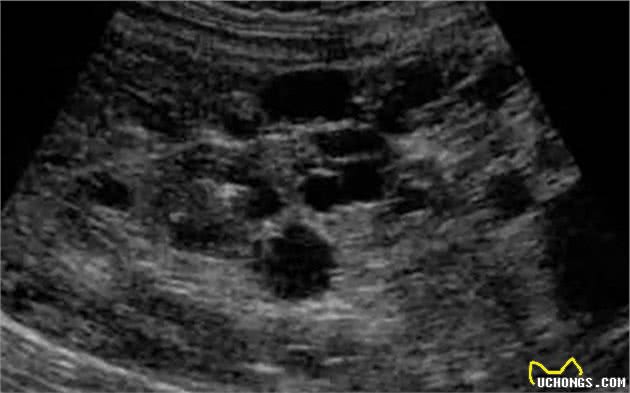

想诊断多囊肾病,用超声波是最快捷的。B超的局限在于没法探查过小的囊肿。在患病猫咪出生之时,肾脏中的囊肿可能只有1mm或者更小,在大小超过2mm之前,一般是难以被察觉的。

在经验丰富的医师手上,B超的准确度不输基因检测,早至两个月大就可以查出猫咪是否患有多囊肾病,但这对医生的水平要求太高,往往不实际。所以用b超检测多囊肾最好等猫咪9至10个月之后,这时候的准确度大致能达到91%到98%。